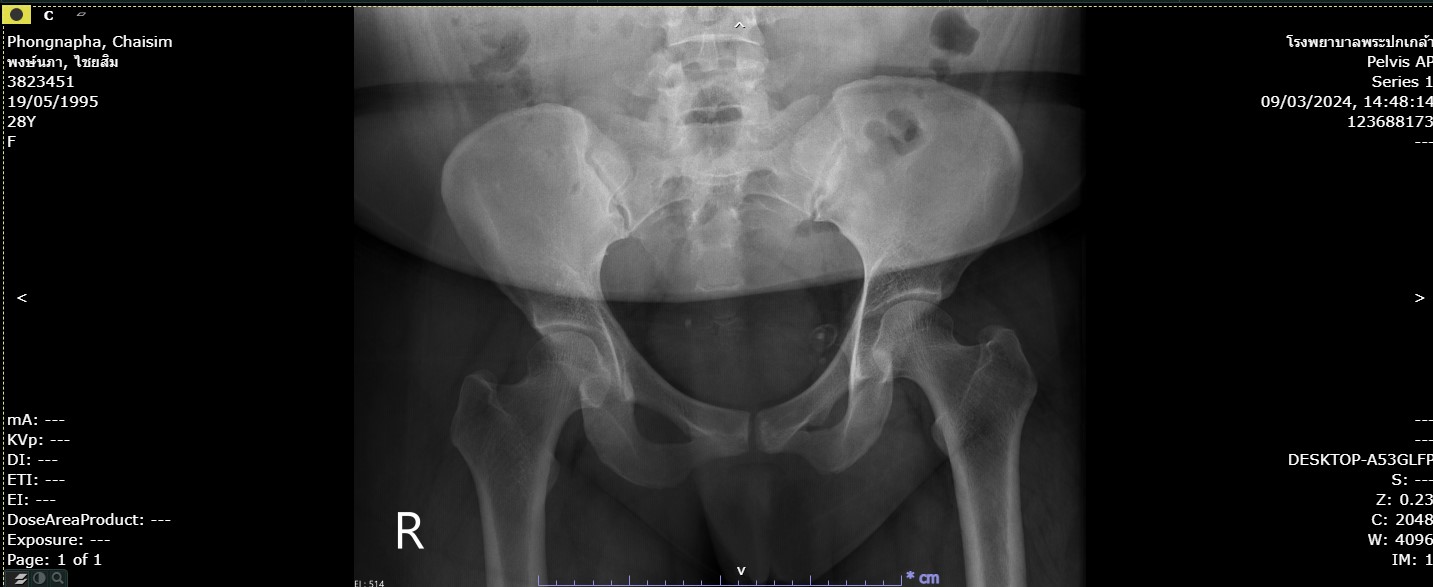

22พงษ์นภา ไชยสิม.jpg     29-Mar-2024 07:50              108774